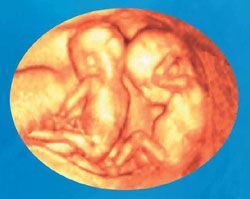

En Ultrasonido Diagnóstico de Hidalgo le brindamos una consulta profesional, realizando Ultrasonido de Embarazo desde su diagnóstico, acompañándole en el crecimiento y desarrollo de su bebe en cada semana de gestación, así como la revisión de los marcadores ultrasonográficos para la detección de alteraciones cromosómicas y estructura del feto. En el primero y Tercer trimestre del embarazo se realiza la revisión de las arterias uterinas para la prevención de la hipertensión de la mujer embarazada.

- Embarazo de alto riesgo

- Sexo del bebe y grabación del bebe

- Embarazo de 13.6 semanas

- Marcadores cromosómicos